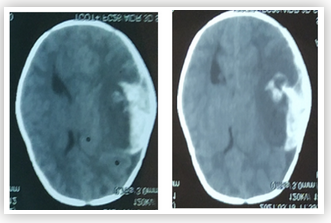

Case Report

Challenges in Diagnosis and Treatment of a Child with Inflammatory Bowel Disease in Resource-Limited Setting - A Case Report

Garba Dayyabu Gwarzo, Muhammad F Bashir, Idris A Adedeji, Adamu S Adamu and Aisha Muhammad